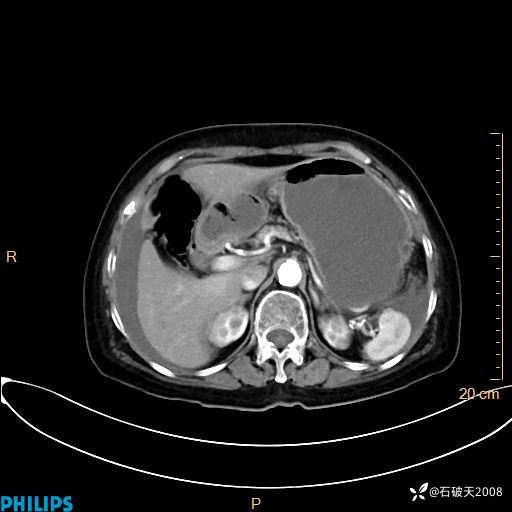

静脉期